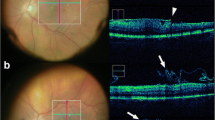

Intraoperative Optical Coherence Tomography

Intraoperative imaging of the retina by optical coherence tomography (OCT) is another advancement in the way vitreoretinal surgeons view the tissue during surgery. OCT imaging allows for micron level resolution of the vitreoretinal architecture presented as cross-sectional images. It plays a core role in the diagnosis and management of retinal vascular disease in the clinic and guides preoperative assessment of many surgical diseases. More than a decade ago, surgeons began studying the ability of OCT to guide intraoperative care. Several commercial systems are now available.

The role of intraoperative OCT has been studied retrospectively since 2009 and now with a prospective 3-year trial [11, 12]. The DISCOVER trial nicely demonstrates subclinical features of vitreoretinal disease and the impact of various surgical manipulation [13, 14]. For example, anatomic success rate for macular hole closure has been associated with intraoperative alteration in the configuration of the macular hole [11, 15]. Overall outcomes have been shown to be equivalent to conventional surgery [16•]. There is some limited evidence that intraoperative OCT imaging can guide the perioperative decision-making, such as confirming the presence of a macular hole discovered immediately following vitreous hemorrhage removal which changed the operative plan for membrane peeling and gas tamponade, or confirming placement of a repositioned IOL despite significant corneal edema [17].